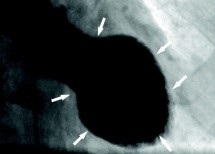

Die Symptome sind identisch. Die Diagnose kann nur durch eine Herz-Katheter-Untersuchung gestellt werden. Bei einem „klassischen“ Infarkt ist eine der drei Herzkranz-Arterien verengt beziehungsweise verschlossen. Bei einem Takotsubo-Syndrom hingegen nicht.

Die Infarkt-Beschwerden werden dadurch ausgelöst, dass das Herz ganz schwach schlägt und der Herzmuskel eine eigentümliche Form hat. Die Herzspitze ist ausgebeult wie ein Ballon.